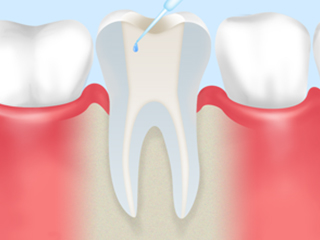

step3

根管内に菌が残らないようにするため、丁寧に消毒を行います。